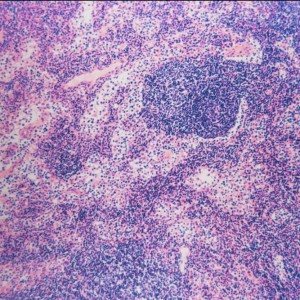

Canine lymphoma, which is one of the most common malignancies diagnosed in dogs, is typically seen as a systemic disease that often involves the lymph nodes, liver, and spleen, and may include the...